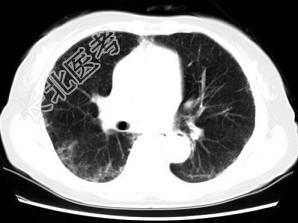

- 单项选择题女,35岁, 咳嗽,咳痰, 发热3月余,胸部CT如图, 最可能的诊断为 ( )

A、类风湿肺炎

B、红斑狼疮性肺炎

C、间质性肺炎

D、肺结节病

E、肺部感染